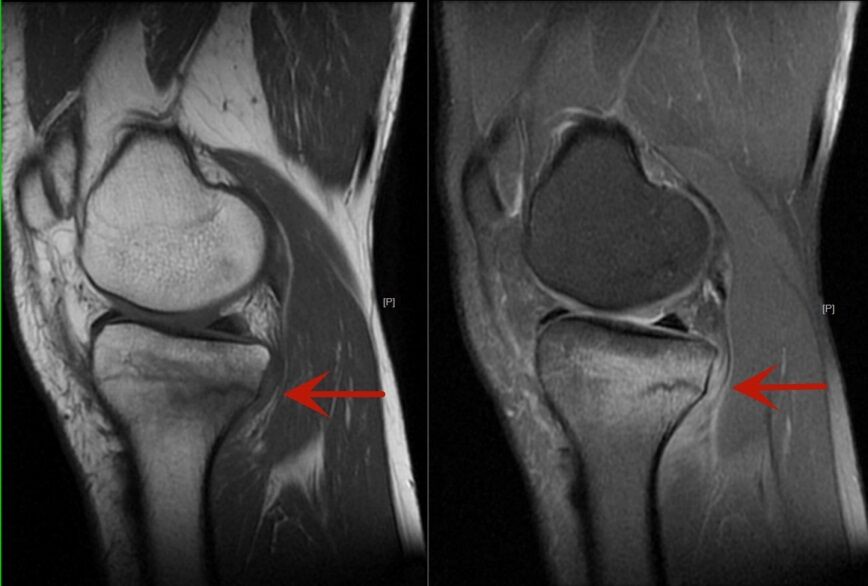

走路也会骨折么?会的。近日,40岁的张先生,自觉双膝疼痛半个月,起初并没在意,可随着日常走路疼痛逐渐加重,于是前来我院放射科拍了X光片(图1),但是并未发现异常,于是又听从医生的建议进行了膝关节的磁共振检查(图2)。最后的诊断结果为应力性骨折。

图2

放射科主任王艳玲表示,一旦有类似活动后疼痛的症状,需要及时来医院就诊,而不是强撑继续活动,以免耽误治疗。建议首诊X线摄片,X线摄片是基础检查,空间分辨率高;除了排查骨折,还要发现骨折以外的病变,对于骨关节磁共振检查不可或缺,磁共振可以发现骨髓水肿,骨挫伤。